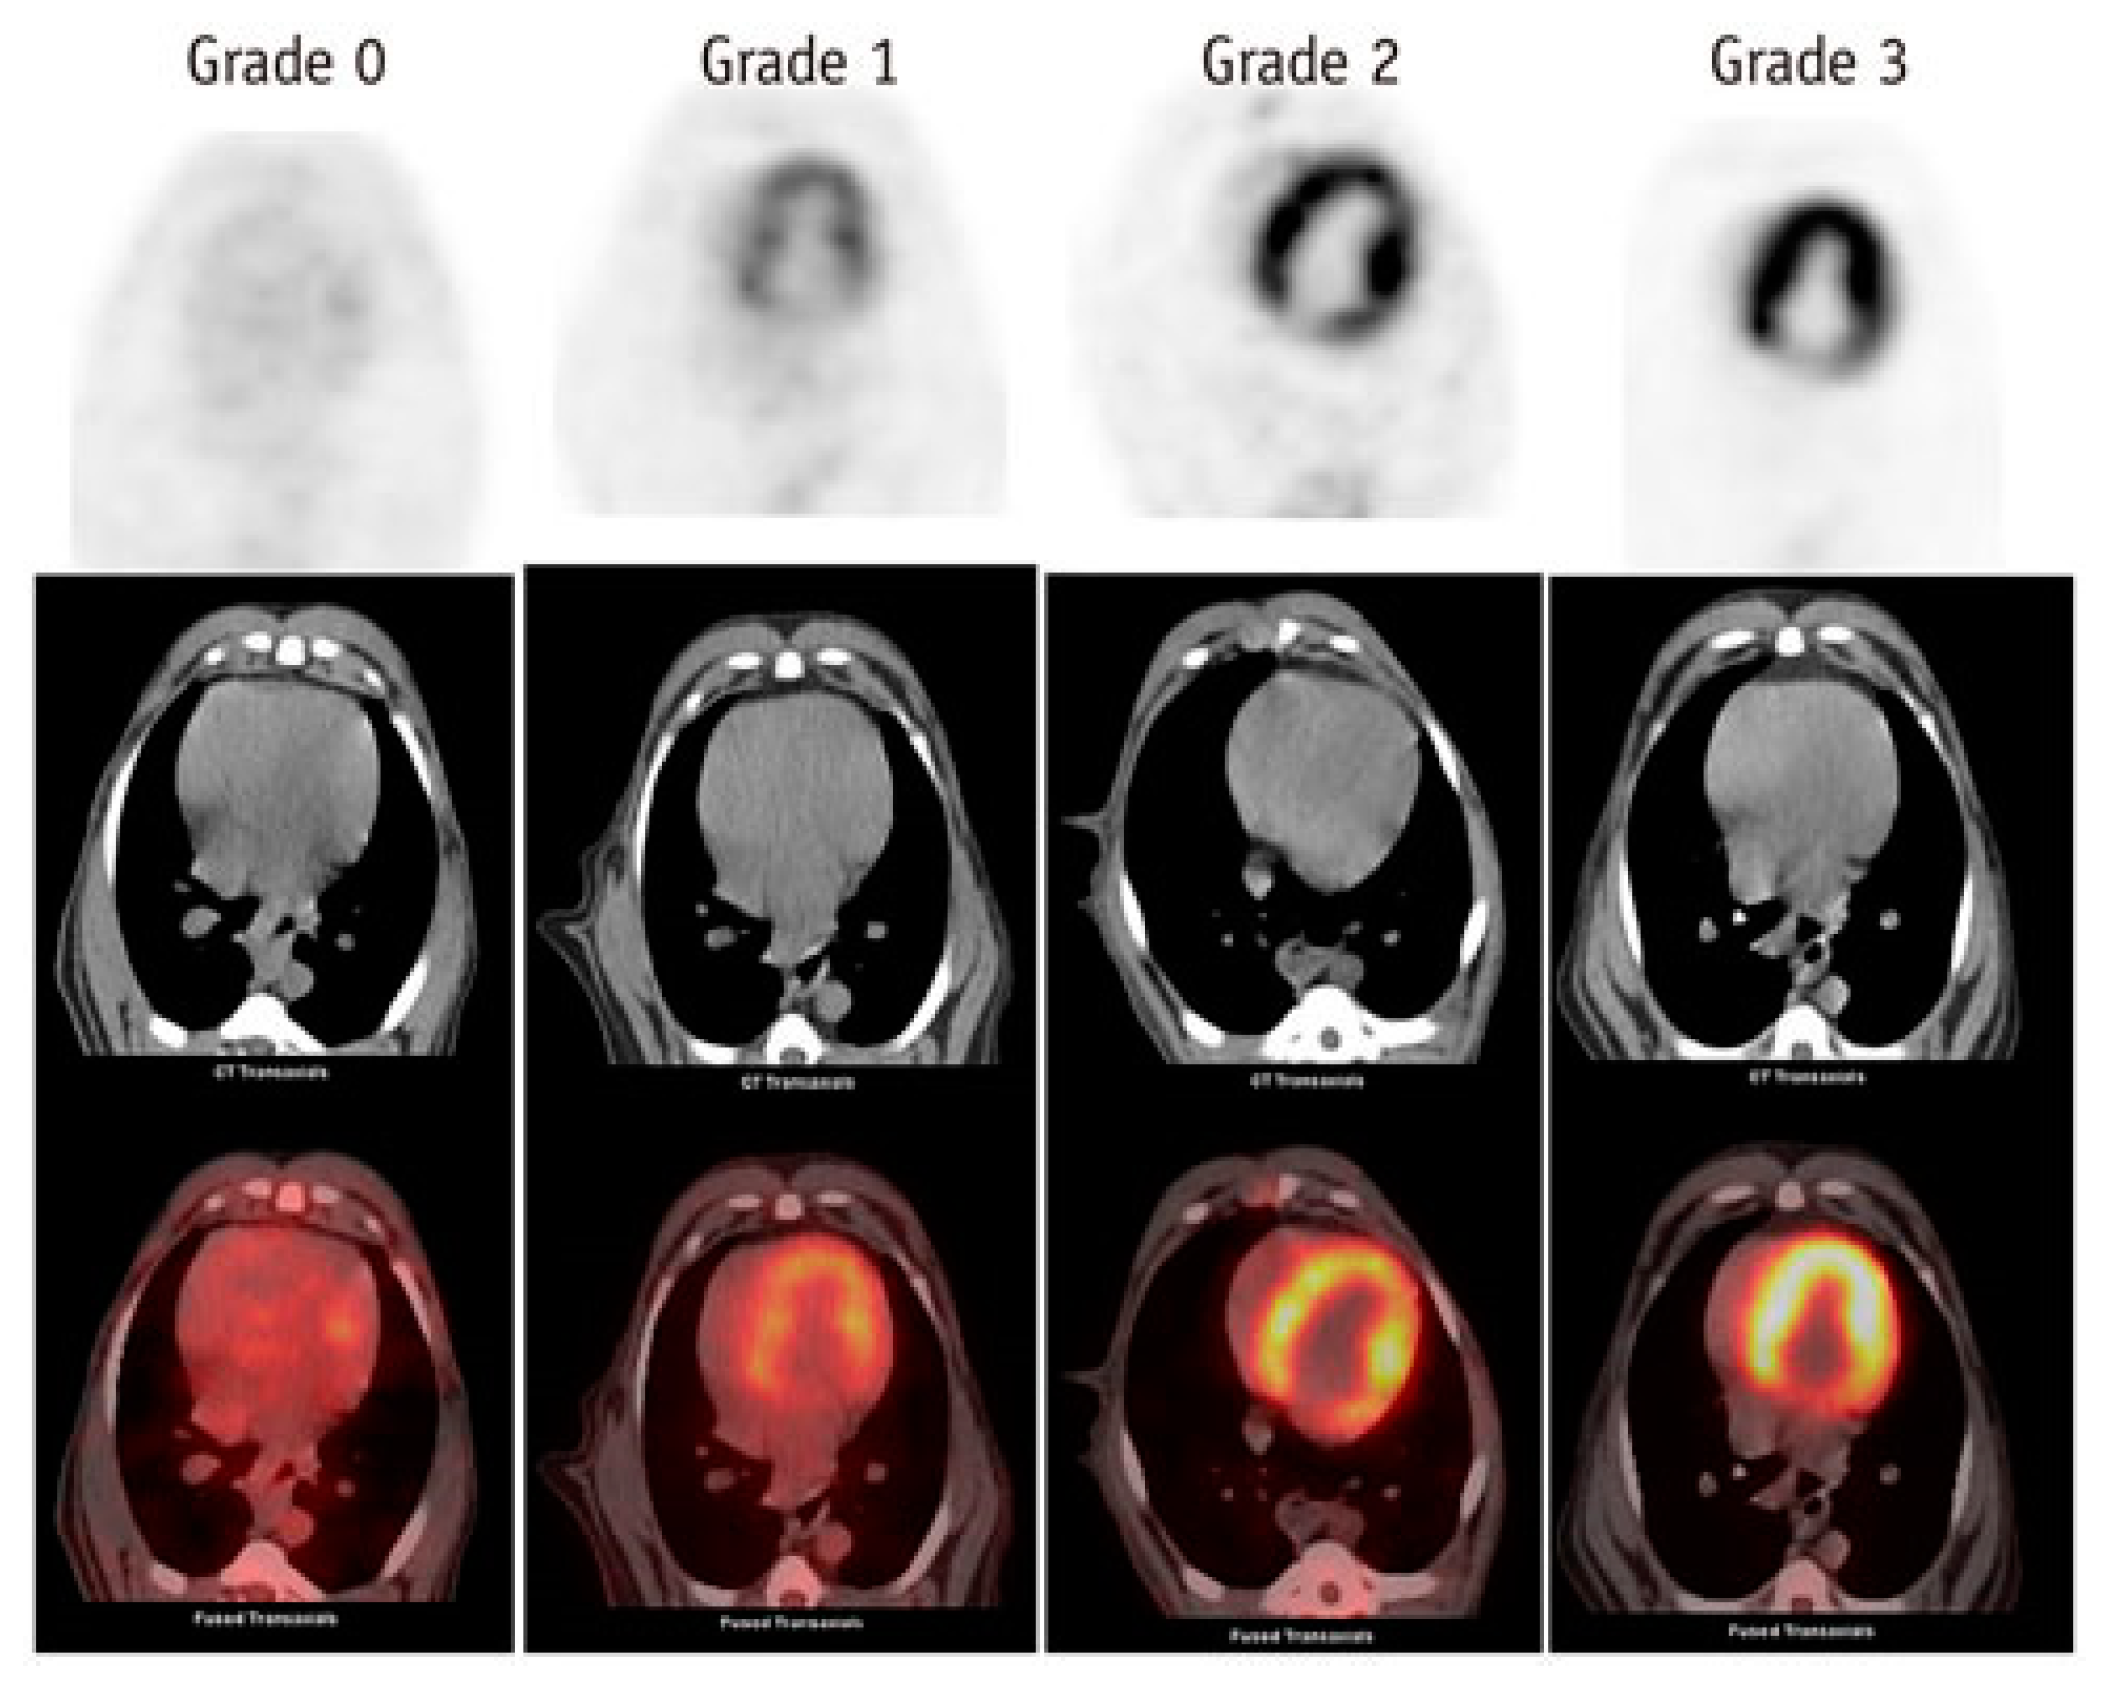

- Sarocchi, M.; Bauckneht, M.; Arboscello, E.; Capitanio, S.; Marini, C.; Morbelli, S.; Miglino, M.; Congiu, A.G.; Ghigliotti, G.; Balbi, M.; et al. An increase in myocardial 18-fluorodeoxyglucose uptake is associated with left ventricular ejection fraction decline in Hodgkin lymphoma patients treated with anthracycline. J Transl Med 2018, 16, 295. [Google Scholar] [CrossRef] [PubMed]

- Bauckneht, M.; Ferrarazzo, G.; Fiz, F.; Morbelli, S.; Sarocchi, M.; Pastorino, F.; Ghidella, A.; Pomposelli, E.; Miglino, M.; Ameri, P.; et al. Doxorubicin Effect on Myocardial Metabolism as a Prerequisite for Subsequent Development of Cardiac Toxicity: A Translational 18F-FDG PET/CT Observation. J Nucl Med 2017, 58, 1638–1645. [Google Scholar] [CrossRef] [PubMed]

- Bauckneht, M.; Cossu, V.; Miceli, A.; Donegani, M.; Capitanio, S.; Morbelli, S.; Marini, C.; Sambuceti, G. FDG-PET Imaging of Doxorubicin-Induced Cardiotoxicity: a New Window on an Old Problem. Current Cardiovascular Imaging Reports 2019, 12. [Google Scholar] [CrossRef]

- Haider, A.; Bengs, S.; Schade, K.; Wijnen, W.J.; Portmann, A.; Etter, D.; Fröhlich, S.; Warnock, G.I.; Treyer, V.; Burger, I.A.; et al. Myocardial 18F-FDG Uptake Pattern for Cardiovascular Risk Stratification in Patients Undergoing Oncologic PET/CT. J Clin Med 2020, 9. [Google Scholar] [CrossRef] [PubMed]